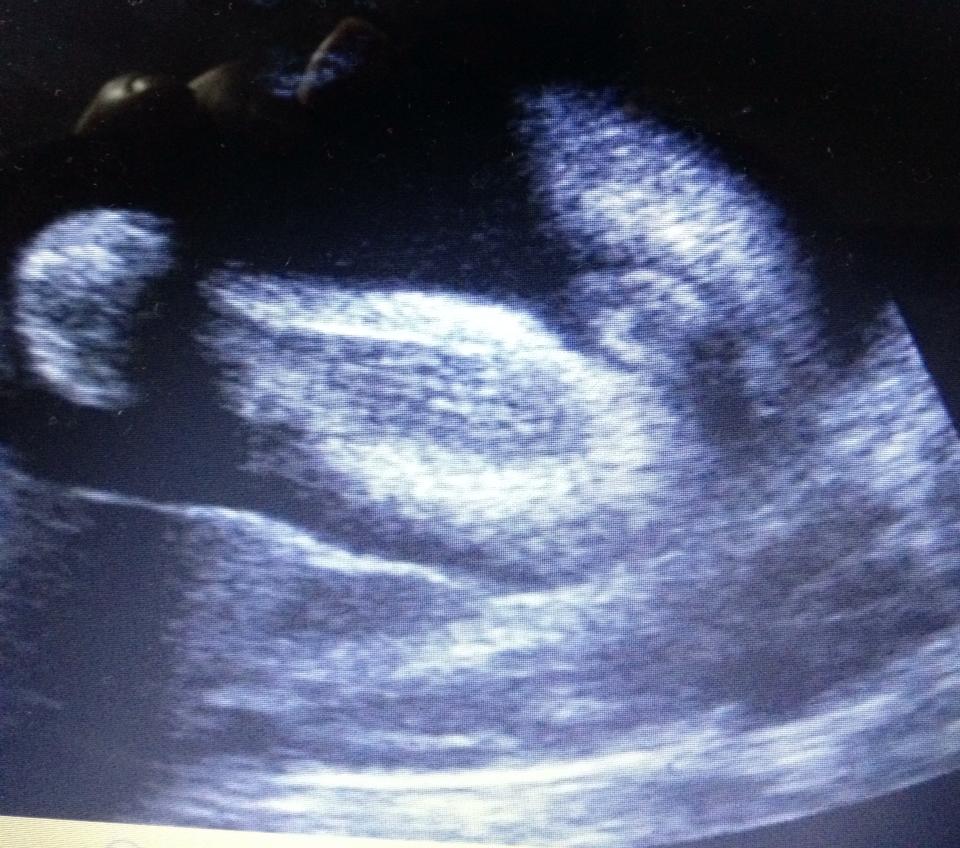

Hi, I've been told it's a boy and a girl... which is it? haha

These scans were taken at 24 weeksAttachment 28867Attachment 28868Attachment 28869

God I hope you're right haha! Depending on the angle it looked girl and other angles it looked boy.... At my 16w they said boy, 19w they said girl "she saw 3 lines" and now these pix at 24weeks lol (I might add - the tech didn't take these pix, I did with the dvd she gave me of the area..).

What is making you think it's a boy? :)

That's my other reasoning too Butterflies buttercups - that it could be swollen girl bits... argh lol! Again, even with the 3d scan I did, some angles showed girl and other angles it showed boy..

I just guessed boy as looks like scrotum bits! Im no expert but I know number 2 of mine had visible balls [emoji23][emoji16] hopefully they're swollen girlie bits as the others have said! How confusing for you to be told different genders [emoji30] surely the later one would be more accurate? X

I also guess girl, at this stage you would see the penis for sure!! How strange the tech could not see / show you the gender at this point. But iI think if it were a boy you would definitely see a penis

I was 24 weeks in these photos.

Could it be a small penis or a huge clitoris..? lol

I'm thinking labia